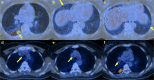

Medical imaging methods are assuming a greater role in the workup of patients with COVID-19, mainly in relation to the primary manifestation of pulmonary disease and the tissue distribution of the angiotensin-converting-enzyme 2 (ACE 2) receptor. However, the field is so new that no consensus view has emerged guiding clinical decisions to employ imaging procedures such as radiography, computer tomography (CT), positron emission tomography (PET), and magnetic resonance imaging, and in what measure the risk of exposure of staff to possible infection could be justified by the knowledge gained. The insensitivity of current RT-PCR methods for positive diagnosis is part of the rationale for resorting to imaging procedures. While CT is more sensitive than genetic testing in hospitalized patients, positive findings of ground glass opacities depend on the disease stage. There is sparse reporting on PET/CT with [18F]-FDG in COVID-19, but available results are congruent with the earlier literature on viral pneumonias. There is a high incidence of cerebral findings in COVID-19, and likewise evidence of gastrointestinal involvement. Artificial intelligence, notably machine learning is emerging as an effective method for diagnostic image analysis, with performance in the discriminative diagnosis of diagnosis of COVID-19 pneumonia comparable to that of human practitioners.